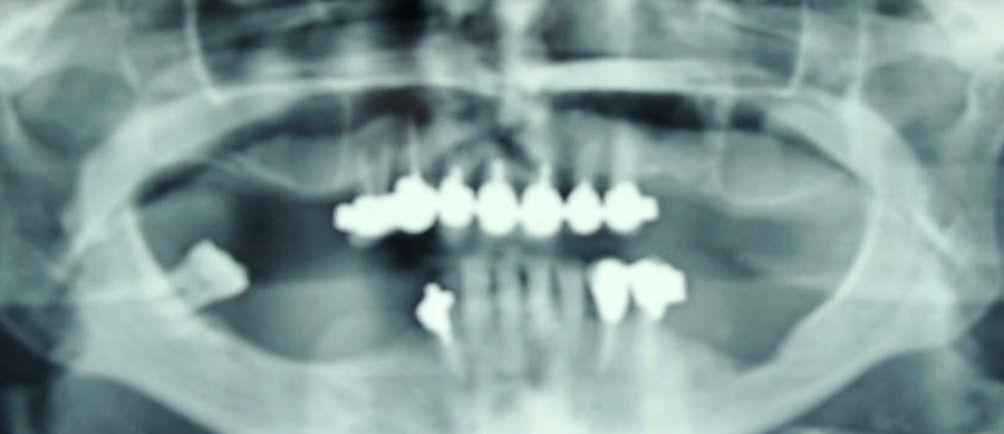

Buccofaringectomia con asportazione di tassello emimandibola sx piu’ linfoadenectomia (pT4 pN0) in associazione con radioterapia.

Rigenerazione ossea del pavimento del seno mascellare con incremento verticale di 12 mm ed orizzontale di 10 mm

Risultati estetici e funzionali conseguiti con la CHIRURGIA RIGENERATIVA